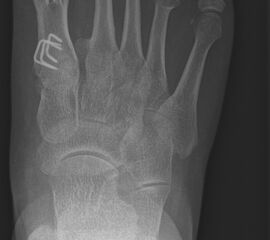

Wachstumsfugen können, wie bereits oben in der generellen Einschätzung des Verfahrens für Kinder und Jugendliche erwähnt, durch direkte Manipulation mit einer Fräse oder indirekt thermisch geschädigt werden. Eine Osteosynthese, die offene Wachstumsfugen kreuzt, ist ausschließlich mit Kirschner-Drähten oder alternativ durch externe Tapezügel möglich. Implantierte Kirschner-Drähte können ohne eine weitere Narkose im Rahmen der Sprechstunde bei verheilter Osteotomie gezogen werden. Die Anwendung von externen Tapezügeln zur Stabilisierung von minimalinvasiven Osteotomien kann bei Kindern ohne Einschränkung durchgeführt werden (siehe Abb. 4 und Abb. 12). Bei sehr jungen Kindern sollten die Tapezügel allerdings nicht zu häufig gewechselt werden, da jeder Verbands- und Tapewechsel Stress für sie bedeutet.

Abb. 12 a-b: Tapezügelfixation nach minimalinvasiver Zehenkorrektur (a) und Röntgenbild nach minimalinvasiver Zehenkorrektur mit kompletten Osteotomien und anschließender Drahtfixation (b).